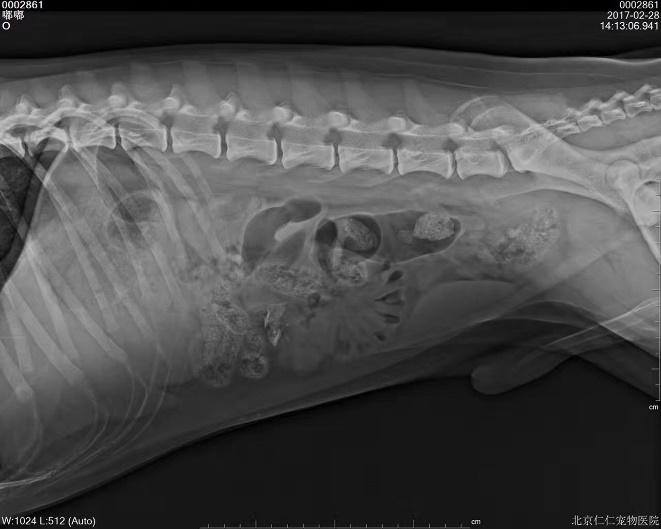

钡餐4小时后胃内未排空(家猫,线性异物)

c.内窥镜:内窥镜可以直观看到胃内容物,因此可以确诊胃内有无异物,以及胃壁是否完整。